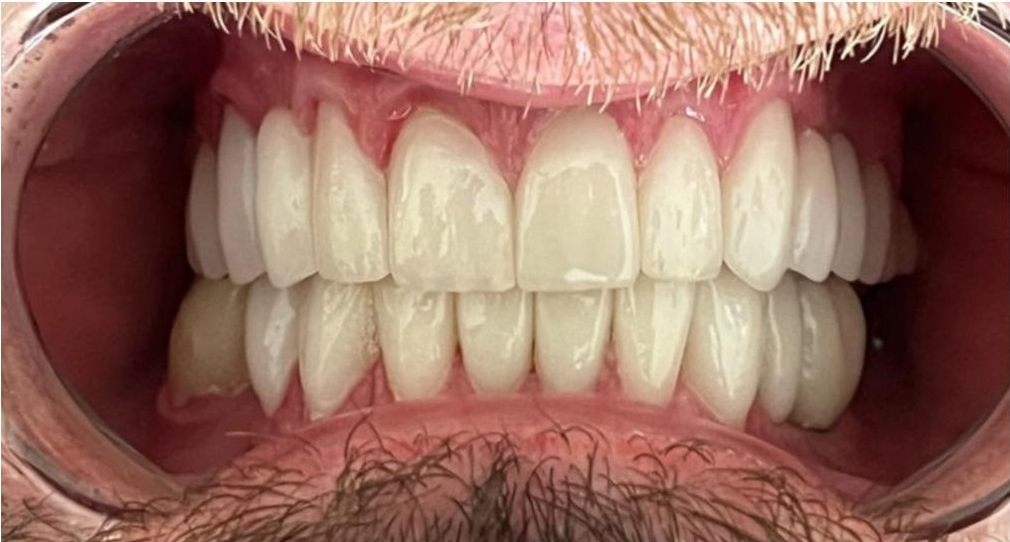

Przeprowadziliśmy precyzyjne leczenie implantologiczne, wszczepiając 11 implantów w szczęce i żuchwie. Konieczna była też regeneracja kości. Po 6 miesiącach gojenia nastąpiła odbudowa pełnołukowa. Kształt, kolor i ustawienie zębów zostały dobrane oraz wykonane na indywidualne życzenie Pacjenta.

Leczenie chirurgiczne i implanto-protetyczne przeprowadził lek.stom. Michał Badowski.

Podczas wizyty lek. stom. Michał Badowski przeprowadził dokładną diagnostykę i przedstawił plan leczenia.

Następnie za pomocą nowoczesnych technologii cyfrowo zaprojektowaliśmy uśmiech, który Pan Bogdan mógł przymierzyć jeszcze przed rozpoczęciem właściwych zabiegów! Później została wykonana kompletna przebudowa zgryzu i uzupełnienie braków zębowych.

Pan Bogdan otrzymał nie tylko nowy uśmiech, ale zupełnie nowe życie!